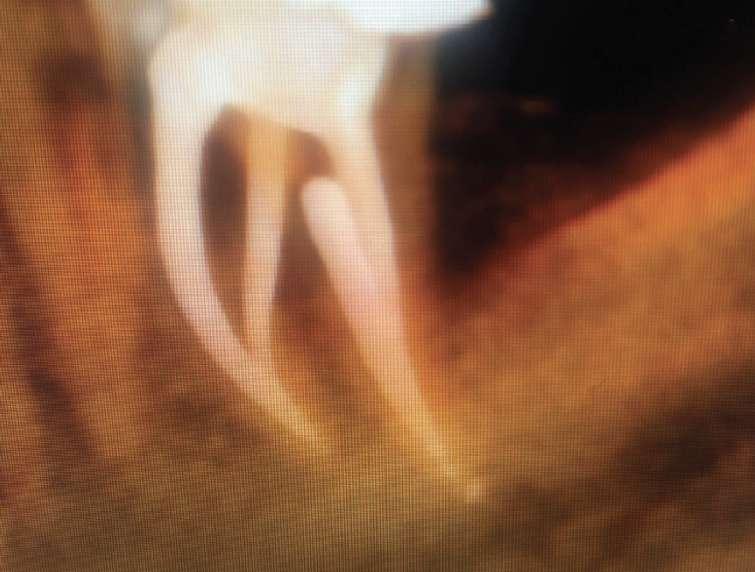

DIVERGIERENDE KANÄLE

Divergierende Kanäle (zwei Kanäle, die zusammen beginnen und sich dann im mittleren / apikalen Teil der Wurzel trennen) stellen ein klinisches Problem in der Endodontie dar, insbesondere bei der Verwendung traditioneller NiTiInstrumente. Aufgrund des superelastischen Verhaltens der Legierung können die Instrumente dem gleichen Kanal folgen (und zwar dem, der gerader ist) aber es ist schwieriger, den zweiten zu finden, insbesondere dann, wenn man den Eingang unmöglich wegen seiner Tiefe in der Wurzel sehen kann.

ZIEL

Der vorliegende Fall zeigt den klinischen Vorteil der Verwendung einer Einzelfeil-Reziprokationstechnik mit einer wärmebehandelten vorgebogenen martensitischen Feile (Edge One Fire) bei der Behandlung divergierender Kanäle auf.

FALLGESCHICHTE

Untere Prämolaren können manchmal zwei oder drei Kanäle aufweisen. Eine solche ungewöhnliche Anatomie ist oft mit engen, stark gekrümmten, konfluenten oder divergierenden Kanälen verbunden. Der letzte Fall ist sehr komplex und erfordert in der Regel den Einsatz von Instrumenten, welche in zwei verschiedenen Kanälen ( daher flexibel und präbendal ) mit unterschiedlichen Winkelstellungen ausgerichtet werden können. Ein angemessener Gleitpfad hilft auch bei der NiTi-Formung, er löst aber nicht immer das Problem. Daher wurde im vorliegenden Fall die primäre EinzelfeileReziproziertechnik EOF verwendet. Die Instrumente wurden in ihrem apikalen Teil vorgeformt, in die beiden verschiedenen Kanäle eingeführt und dann aktiviert. Die Wahl der Instrumente war effektiv, weil die mechanischen Eigenschaften des EOF-Primärs (flexibel und vorgebogen) es ermöglichen, präzise und einfach in jeden Kanal eingeführt zu werden und diese dann zu behandeln. Die Verwendung einer einzigen Feiltechnik ermöglichte es, sich der Herausforderung eines divergierenden Kanals nur einmal zu stellen, was Zeit spart und die Komplexität reduziert. Die Verwendung traditioneller Instrumente kann in vielen Fällen helfen, den Weg mit kleineren und flexibleren Instrumenten zu finden, aber nicht mit größeren. Durch die Verwendung von nur einer Feile erwies sich das gesamte Verfahren als einfacher und schneller, sodass beide Kanäle korrekt geformt, gereinigt und abgedichtet werden konnten.

Eine Single-File-Reziprozierungstechnik mit einer wärmebehandelten vorgebogenen martensitischen Feile (Edge One Fire) erwies sich als ausgezeichnete, einfache und schnelle Option für die Instrumentierung von divergierenden Kanälen.

SCHLUSSFOLGERUNGEN

Komplexe Kanalanatomien erfordern den rationalen Einsatz von NITIInstrumenten, indem die beste Option für den Fall in Bezug auf Effizienz, Sicherheit und Einfachheit ausgewählt wird. Die mechanischen Eigenschaften von EOF ermöglichen es, divergierende Kanäle mit großer Wirksamkeit zu behandeln, wobei iatrogene Fehler oder Komplikationen vermieden werden können.